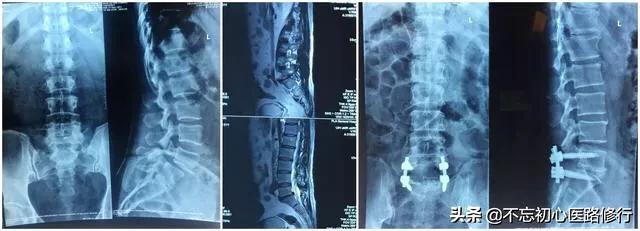

2.後方開放プレート除圧ペディキュラースクリュー内固定術。

通常、椎弓切除術で解決できない手術も、この手術で解決できる。

椎間板ヘルニアを摘出すると、椎骨間の安定性の一部が失われるため、腰痛を引き起こすだけでなく、腰の変性が促進される可能性があるからです。そこで、すでに腰が不安定な高齢の患者さんには、椎間板をすべて取り除き、癒合器具を装着して腰を内固定で固定する、1回きりの癒合手術が可能です。この手術のリスクは、椎間板の摘出だけよりも大きくなります。

腰椎椎間板ヘルニアの多発性、重圧迫、より複雑な椎間板ヘルニアに適している。手術のリスクを除くと、いわゆる手術の失敗として考えられるのは、内固定具のゆるみ、抜去、切開部の治癒不能などである。このようなケースはめったにない。